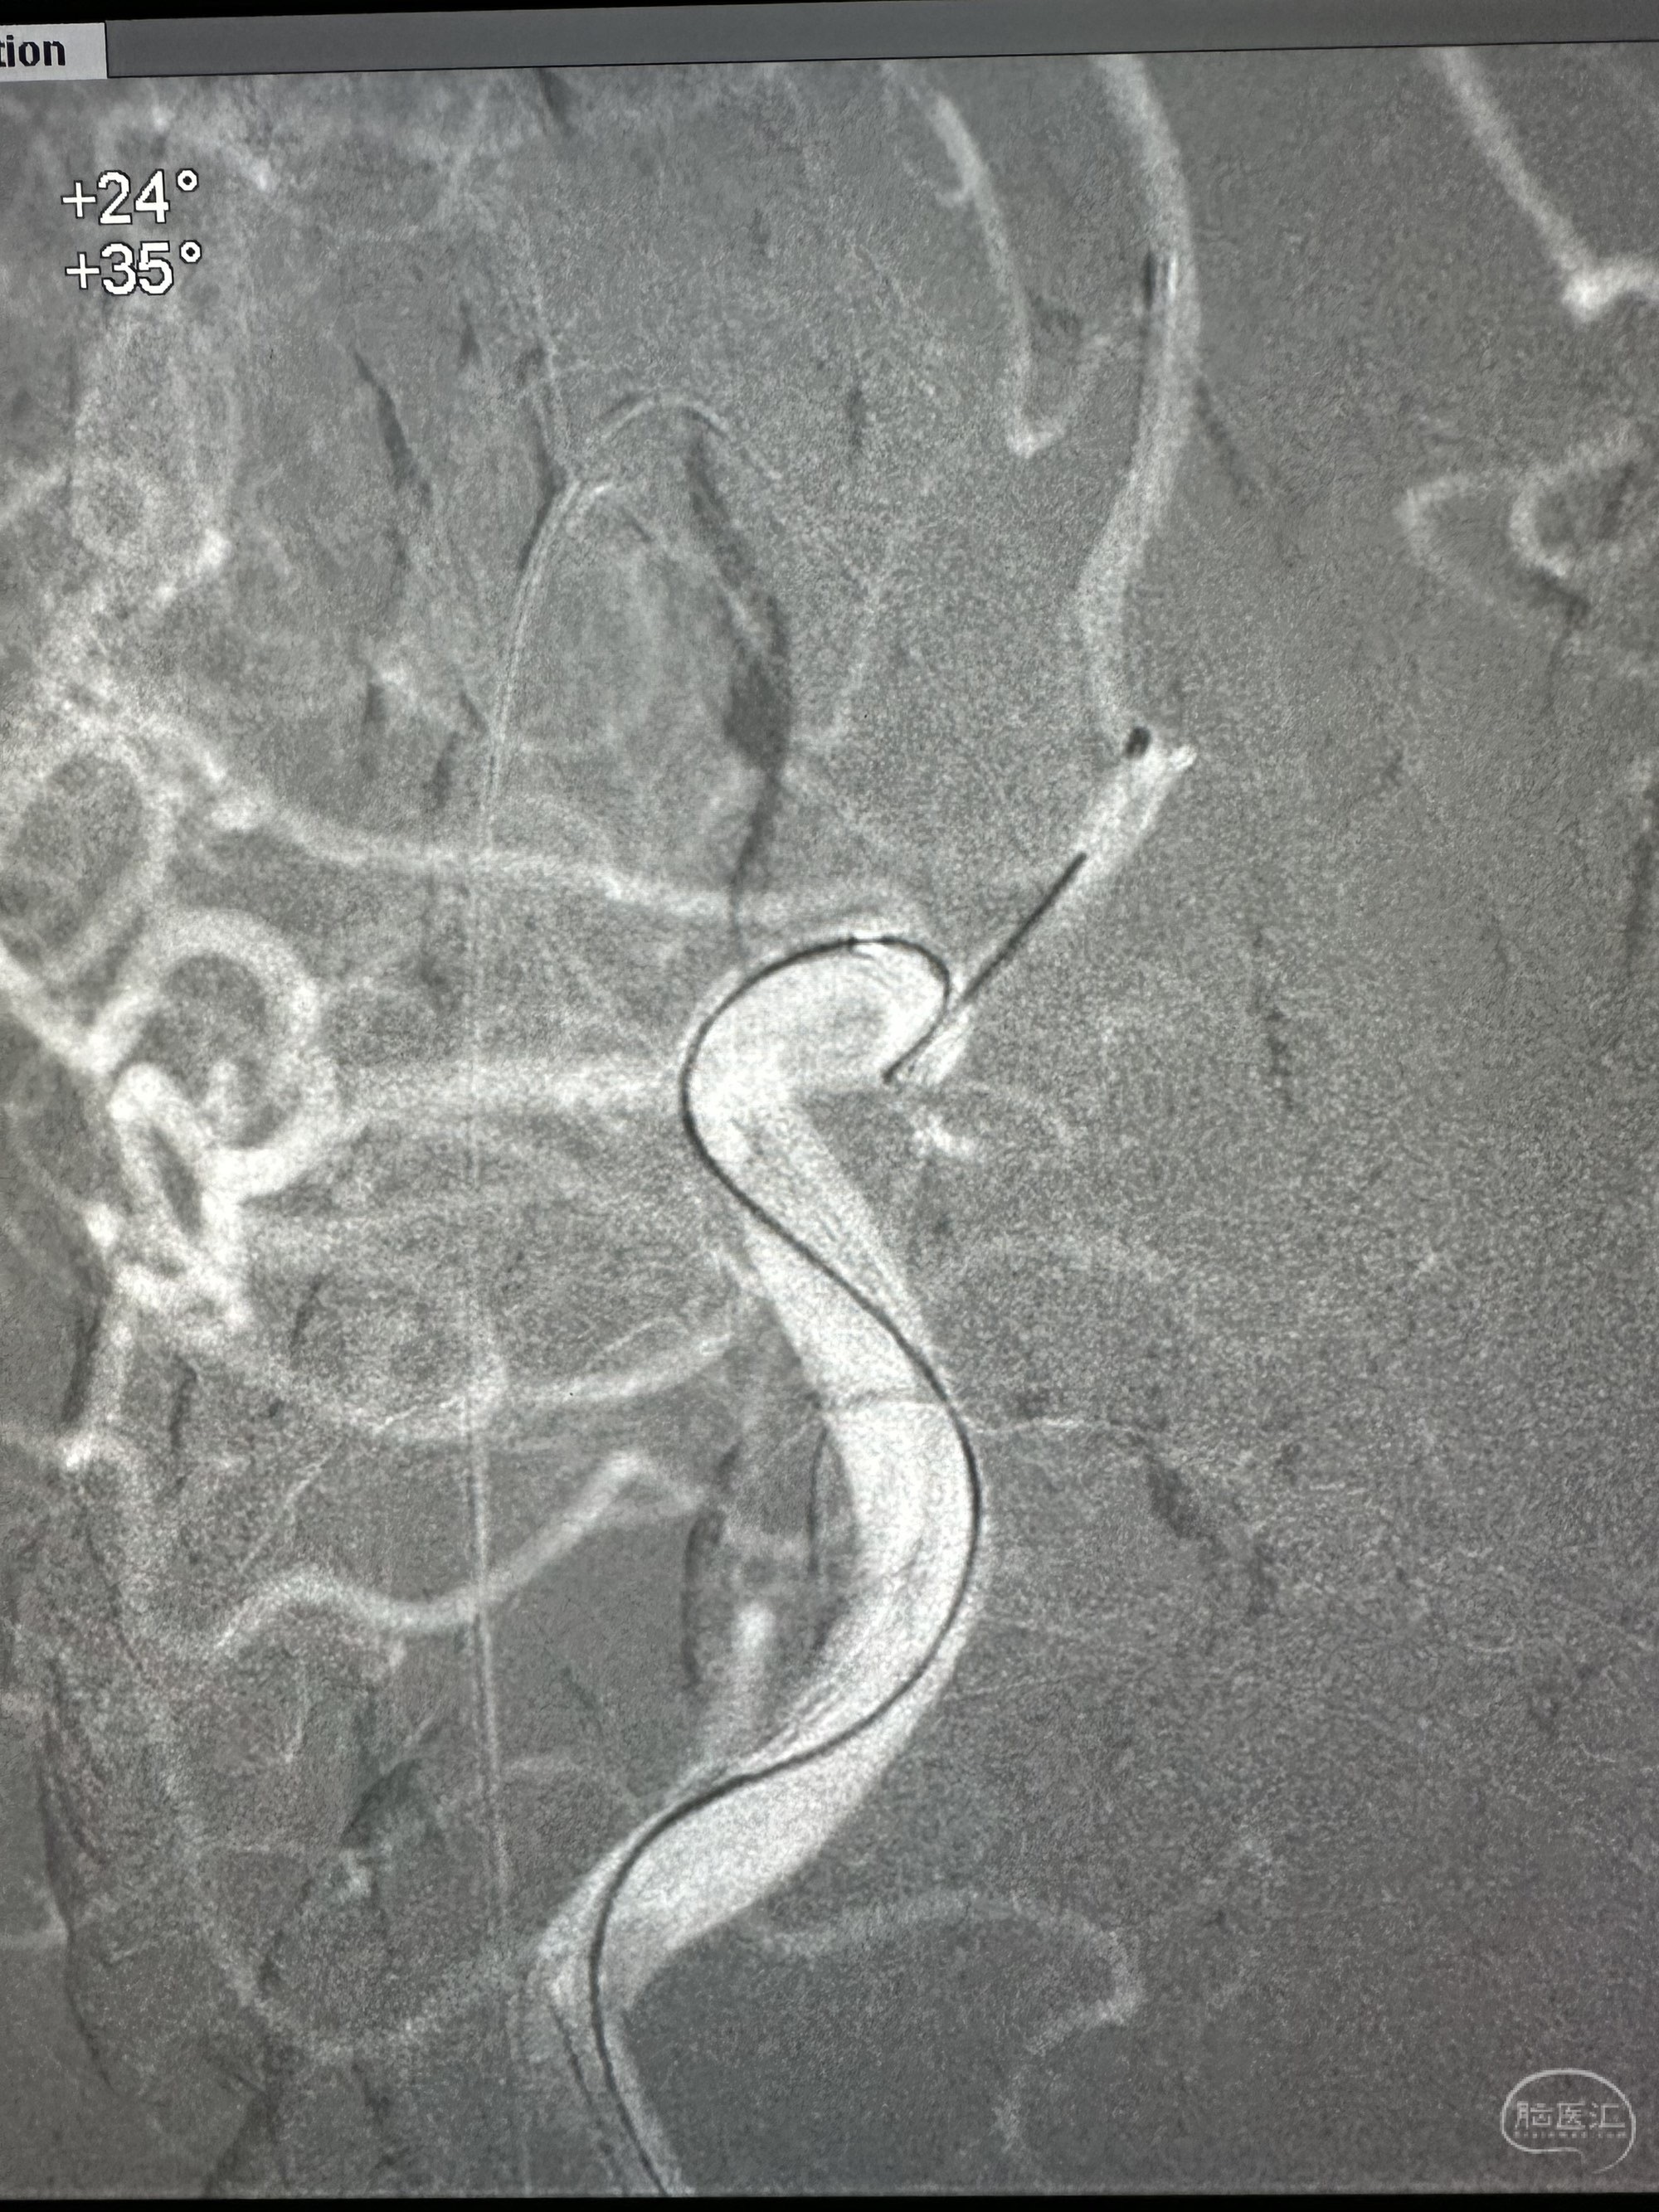

Plus支架导管到位,enchon 10直头小心接近动脉瘤,动脉瘤显影不太好

微导管到位后